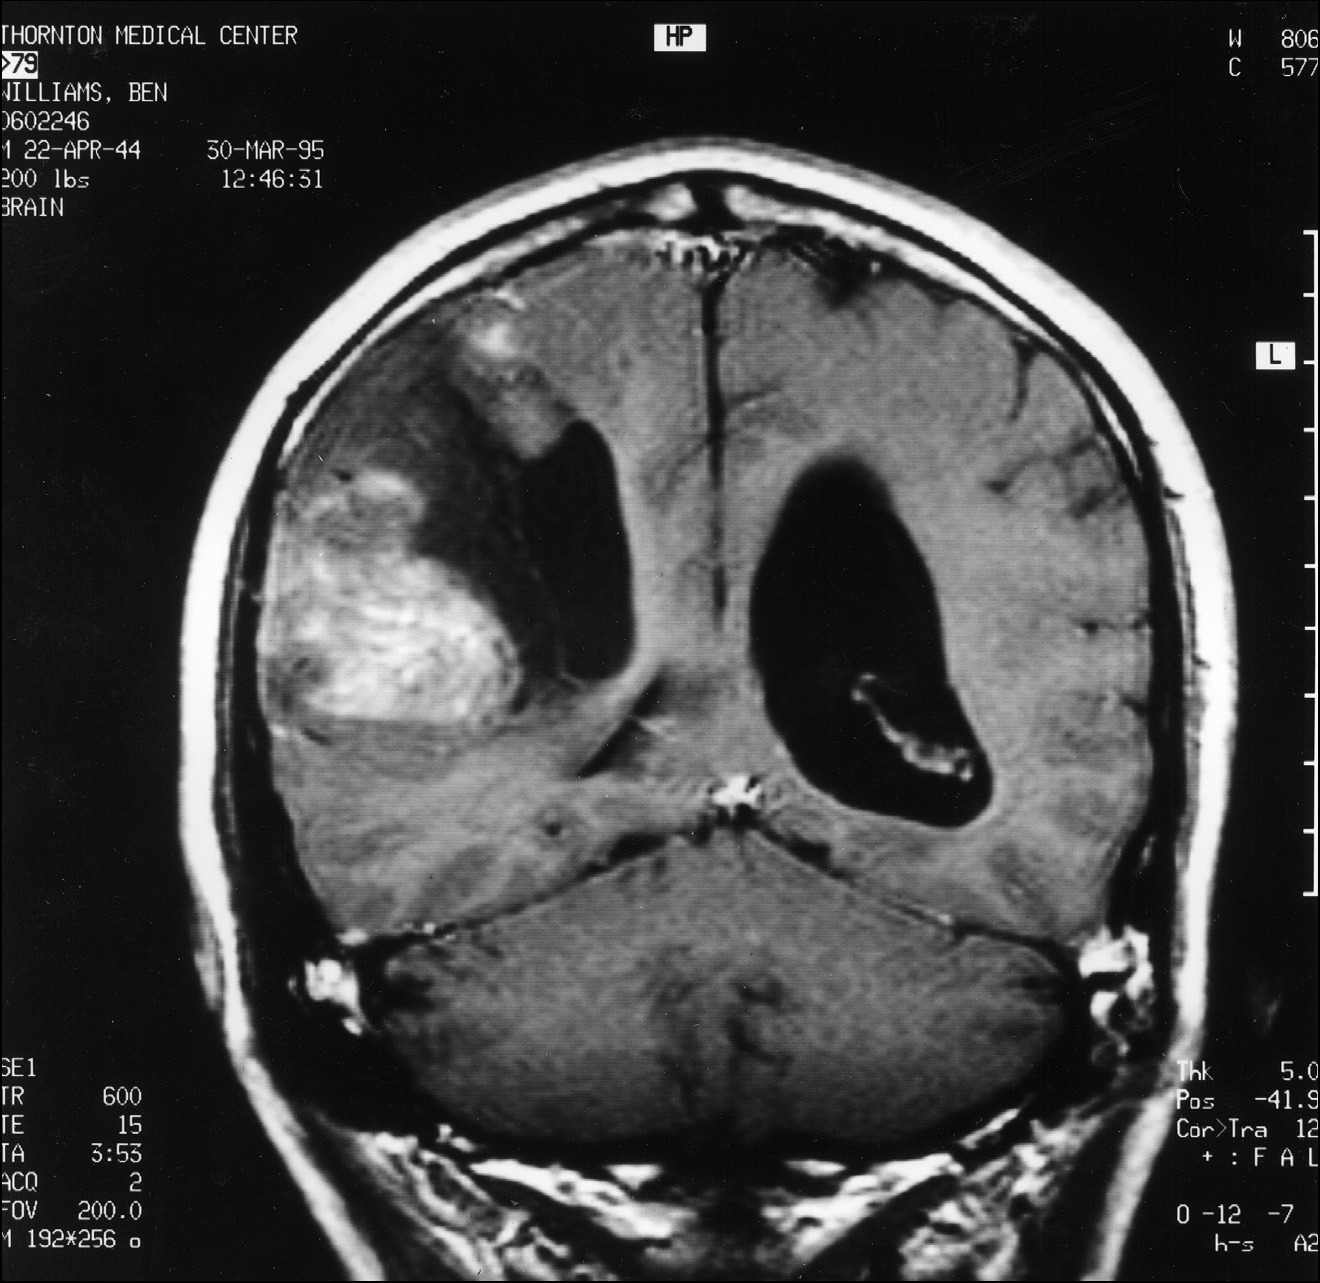

MRT pateikia smegenų skenavimų seriją, fiksuojančią smegenų pjūvius nuo viršaus iki apačios, iš šono į šoną ir iš priekio į galą. Šiam konkrečiam tyrimui visos trys serijos buvo pateiktos du kartus – vieną kartą prieš man gaunant gadolinio injekciją ir vieną kartą po jos. Gadolinis yra kontrastinė medžiaga, kurią absorbuoja naviko audinys, bet ne normalus smegenų audinys. Jei navikas yra, gadolinis MRT vaizde atrodo kaip ryškiai baltos dėmės; kuo ryškesnės dėmės, tuo sparčiau navikas auga. Tai taip pat parodo, kiek naviko yra.

Kai MRT pagaliau baigėsi, pradėjau rinkti savo daiktus, bet technikas Patrick pasakė, kad gydytojai norės mane pamatyti nedelsiant. Iš to supratau, kad jis skenavimo metu pastebėjo kažką labai rimto. Kai grįžau į priėmimo skyrių, rezidentas neurologas žiūrėjo MRT vaizdus monitoriuje. Jam akivaizdžiai buvo sunku pasiruošti pranešti blogą žinią, todėl vietoj to pakvietė mane kartu pažiūrėti į skenuotus vaizdus. Buvau priblokštas. Visa dešinioji smegenų pusė buvo naviko apimta (žr. čia ir čia). Akimirką atsigavęs, pakomentavau: „Bent jau dešinėje pusėje." Buvau matęs, kokie pražūtingi gali būti kairiojo pusrutulio pažeidimai. Neurologas pritarė mano pozityviam požiūriui, tačiau buvo aišku, kad, jo manymu, netrukus mirsiu.

1 pav.

MRT pjūvis, atliktas per smegenų vidurį tarp priekio ir galo.

2 pav.

MRT pjūvis, atliktas per smegenų vidurį tarp viršaus ir apačios. Panašūs naviko kiekiai buvo matomi bent pusėje abiejų serijų pjūvių.

Matyt, tokie dideli ir grėsmingi smegenų navikai kaip manasis yra reikšmingas įvykis. Netrukus pusė neurologijos skyriaus susirinko apžiūrėti vaizdų. Mano neurochirurgas apibūdino naviką kaip didelio apelsino dydžio; mano neuroonkologas vėliau apskaičiavo jo tūrį – 184 kubinius centimetrus.